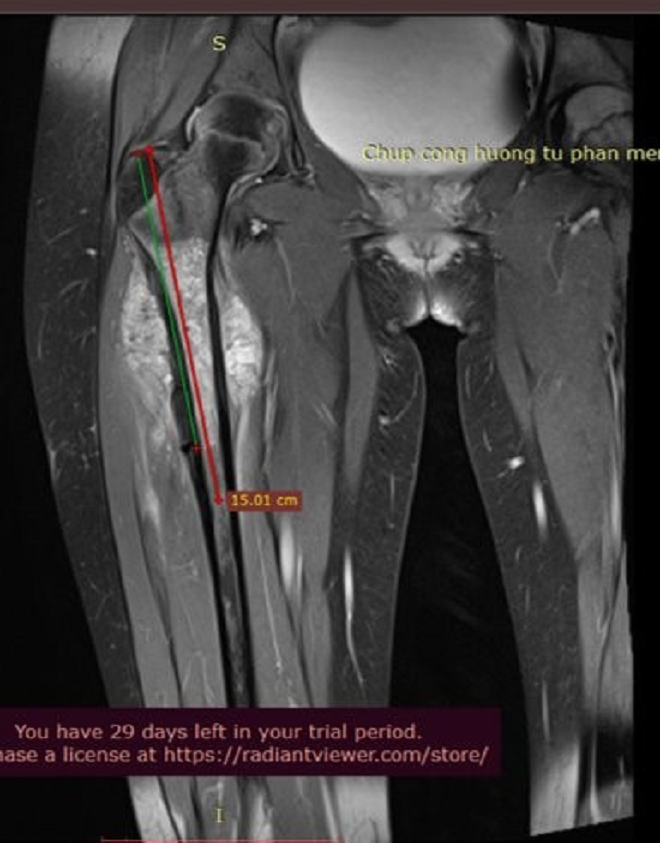

Ảnh chụp cộng hưởng từ khối u cháu Ngọc Hoa được điều trị hiệu quả và tích cực tại Vinmec.

Khác với Khánh Thơ, bệnh nhân Ngọc Hoa (9 tuổi, Hà Nội) cũng phát hiện bệnh ở giai đoạn 2B, nhưng nhờ được điều trị chuẩn đã có tiến triển tích cực hơn nhiều. Ngay khi phát hiện K xương vào tháng 11/2022, cháu được bố mẹ đưa đến điều trị tại Trung tâm CTCH Vinmec. Toàn bộ quá trình chẩn đoán điều trị từ sinh thiết, phẫu thuật, hóa trị trước và sau phẫu thuật được trung tâm chuyên sâu về ung thư xương Vinmec tiến hành rất bài bản trong vòng 9 tháng.

Nhờ sử dụng đúng liều hóa chất trong môi trường điều trị đảm bảo chất lượng, tỉ lệ hoại tử u của bệnh nhân Ngọc Hoa đạt đến 100% - mức độ tế bào ung thư chết toàn bộ. Đến nay, sau 6 tháng kể từ khi kết thúc đợt hóa trị bổ trợ cuối cùng, bệnh nhân không có dấu hiệu di căn.